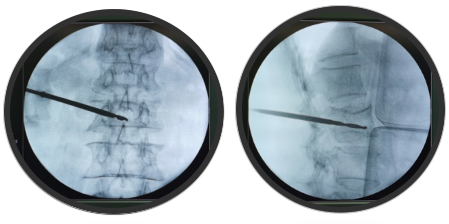

传送图像,规划腰2椎弓根钉钉道,沿机器人导向器,钻入导针,插入工作套管

C臂透视侧位钻头前端位于椎体前1/3,正位过椎体中线

插入球囊扩张器,注入造影剂

注入骨水泥,透视可见椎体高度恢复满意,骨水泥分布良好

此次机器人手术中,先由C型臂对患者进行三维影像扫描,图像被同步传输至手术机器人系统。医生在导航系统屏幕上设计好钉道,沿机器人导向器,钻入导针,插入工作套管。C臂透视侧位钻头前端位于椎体前1/3,插入球囊扩张器,注入骨水泥,透视可见椎体高度恢复满意,骨水泥分布良好。手术非常成功。